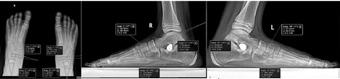

Figura 1 – Măsurători radiologice post-operator, din față și din profil, la un pacient pediatric operat cu procedura Grice

Figura 2 – Măsurători radiologice post-operator, din față și din profil, la un pacient pediatric operat cu procedura Artroerezis

Am analizat retrospectiv pacienții operați în cadrul clinicii noastre pentru picior plat simptomatic între anii 01.01.2013 –01.05.2024 (11 ani). În total, au fost incluși peste 150 de pacienți, dintre care 123 au beneficiat de arthroereisis, iar 34 de procedura Grice. Criteriile de includere au presupus: vârsta pediatrică, deformare simptomatică, lipsa răspunsului la tratament conservator. Examinările radiologice au fost realizate cu piciorul în încarcare si au fost măsurate unghiurile Meary, Kite și Pitch-ul calcanean în radiografia de profil, iar pe radiografia de față unghiul Kite si cel de descoperire al astragalului. Evaluarea clinică s-a bazat pe

• În grupul arthroereisis (n≈123), unghiul Meary a scăzut în medie de la 13° la 4° postoperator, iar unghiul pitch calcanean a crescut de la 11° la 18° (p<0,001 pentru ambele). Aproximativ 85% dintre pacienți au raportat dispariția completă a durerii la 6 luni postoperator.

• În grupul Grice (n≈34), unghiul Meary a scăzut de la 15° la 5°, iar pitch-ul a crescut de la 10° la 16° (p<0,01). Corecția s-a menținut stabilă la controalele la 12 luni.

• Comparativ, pacienții cu arthroereisis au reluat mersul fără durere în medie după 3 săptămâni, în timp ce după Grice acest interval a fost de aproximativ 6 săptămâni (p<0,01).

Complicațiile au fost rare: în grupul arthroereisis, ≈4% dintre pacienți au necesitat explantarea implantului din cauza durerii persistente, cu evoluție bună ulterior; în grupul Grice, ≈12% au avut

consolidare întârziată a grefei osoase, rezolvată conservator.